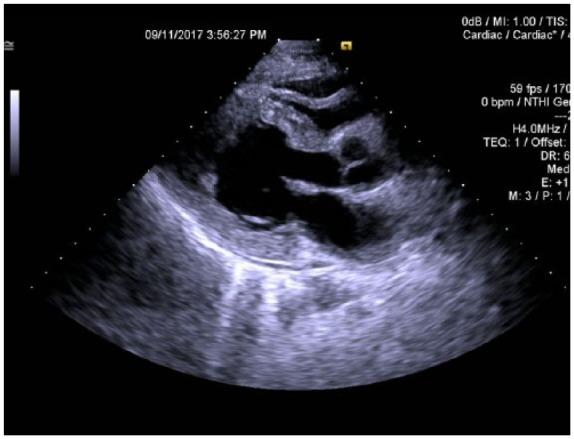

Eosinophilic myocarditis is an infiltrative disease that affects the myocardium leading to various presentations. It can be precipitated by medications, helminthiasis, or hypereosinophilic syndrome. We present the case of a young, male patient who presented with palpitations and dyspnea and was found to have heart failure with reduced ejection fracture of 12%. His past medical history was significant for recent lung problem treated with steroids. Based on his history and laboratory findings, he was started on intravenous steroids for treatment of eosinophilic myocarditis. Within 3 days, his ejection fracture improved to 35%. Given the nonspecific clinical presentations, mimicking other diseases, high index of suspicion is warranted to diagnose eosinophilic myocarditis. This is crucial as early detection and treatment with steroids can lead to a dramatic response.

嗜酸性粒细胞性心肌炎是一种浸润性疾病,可累及心肌并导致多种临床表现。它可能由药物、蠕虫感染或高嗜酸性粒细胞综合征引发。我们报告了一例年轻男性患者,该患者出现心悸和呼吸困难,经检查发现患有心力衰竭,射血分数降低至12%。他的既往病史显示近期因肺部问题接受了类固醇治疗。根据他的病史和实验室检查结果,开始给予静脉注射类固醇治疗嗜酸性粒细胞性心肌炎。3天内,他的射血分数提高到了35%。鉴于嗜酸性粒细胞性心肌炎的临床表现不具特异性,易与其他疾病混淆,因此需要高度怀疑以诊断该病。这至关重要,因为早期发现并用类固醇治疗可产生显著疗效。